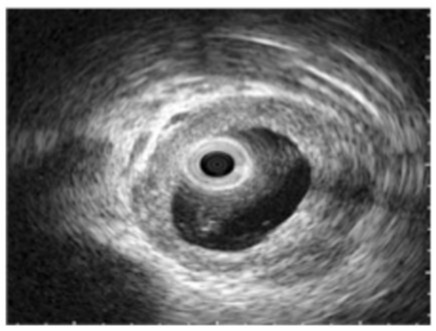

The pathology of IgG4‐SC shows sclerosing fibrosis and infiltration of lymphoplasmacytic with IgG4-positive plasma cells of bile duct [16]. IgG4‐SC is strongly suggested to cause stenosis however thickened bile duct wall with smooth outer margin without stenosis ( visible lumen ) are more commonly seen in IgG4-SC patients, figure 2 [17]. Most cases of IgG4‐SC that are associated with autoimmune pancreatitis shows stenosis of the lower bile duct the cause of which is still unknown and can be mostly due to pancreatitis enlargement or IgG4-SC. Gallbladder lesion of IgG4-related disease which present as thickened wall of the gallbladder is considered as a significant difference between IgG4‐SC and CCA. Thickened wall of the gallbladder is strongly suggestive of IgG4‐SC [17-19]. Cholangiocarcinoma is an adenocarcinoma which is a malignant epithelial neoplasm arising from the biliary tree. Usually, CCA causes obstruction of bile duct which lead to obstructive jaundice and there is increase of serum total bilirubin levels [17]. CCA does not involve other organs unless it is metastasized. Some cases of CCA shows abundant infiltration of IgG4-positive plasma that mean infiltration of IgG4-positive plasma is not specific for IgG4-SC and hence could not be diagnosed as IgG4-SC only by immunostaining (Figure 2) [17,20-22].

Figure 2: Intraductal ultrasonography shows wall thickness with smooth outer margins in the bile ducts without stenosis in immunoglobulin G4-related sclerosing cholangitis patients [17].

Ultrasound [US]) is done as initial investigation for most patients who are thought to have IgG4‐SC or CCA [3,23]. Usually US finding are normally in the early stages of IgG4‐SC but in the late stages it will show circumferential wall thickening of the bile duct without stenosis and dilatation of intrahepatic bile ducts [3,24]. Also, US helps in the identification of associated findings in gallbladder and pancreases. Intraductal US (IDUS ) of IgG4‐SC shows high accuracy of imaging of the duct wall. IDUS shows diffuse symmetric homogeneous wall thickening with smooth margins and the lumen is preserved [10,25]. On IDUS, the cutoff value of bile duct wall thickness without strictures is 0.8mm and it is a characteristic feature of IgG4‐SC (sensitivity 95-100% and specificity 91%) and it is an important feature which can help to differentiate IgG4‐SC from cholangiocarcinoma [10,25,26]. The finding of CT and MRI in IgG4‐SC and CCA mostly same in US but more accuracy in CT and MRI. CT and MRI finding of IgG4‐SC was circumferential symmetric bile duct wall thickness with smooth inner and outer margin, and lumen is visible [3,27,28]. These findings can be used to differentiate between IgG4‐SC and CAA (80% sensitive, 90% specific) [3,26,27].